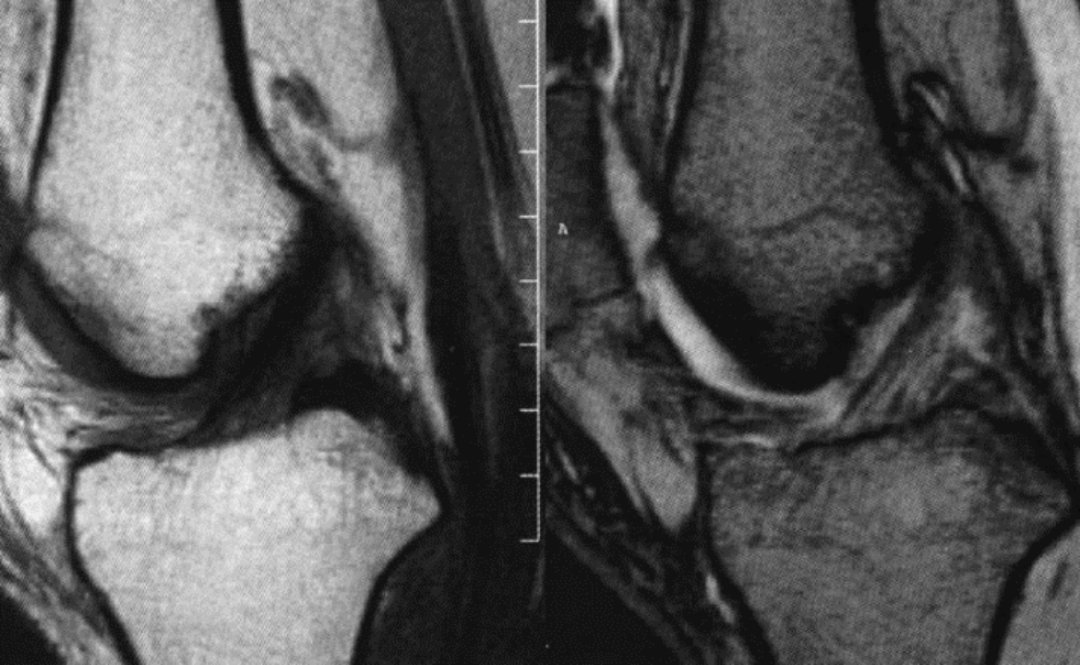

女,65 岁,左膝关节前交叉韧带损伤,膝关节积液,T1 及 T2 加权序列前交叉韧带信号增高,但韧带纤维束完整外形无明显改变

男,50 岁,前交叉韧带部分损伤,T1 及 T2 加权序列,韧带信号明显增强,形状略不规则,纤维束部分仍连续

病例 2:

女,54 岁,左膝关节前交叉韧带部分撕裂,左侧胫骨上段骨折伴骨髓水肿,矢状面 T1 加权序列,冠状面及矢状面 T2 加权序列,韧带信号增高,部分纤维束连续